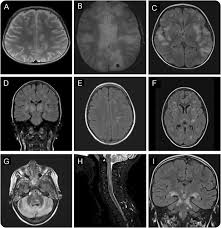

Demyelinating Disease : Putative Association Of Gpc5 Polymorphism With The Risk Of Inflammatory Demyelinating Diseases Journal Of The Neurological Sciences - Chronic inflammatory demyelinating polyneuropathy (cidp) is a neurological disorder characterized by progressive weakness and impaired sensory function in the legs and arms due to impaired myelin.. Chronic inflammatory demyelinating polyneuropathy (cidp) is a neurological disorder characterized by progressive weakness and impaired sensory function in the legs and arms due to impaired myelin. Demyelination describes the loss of the myelin sheath, where sc are being destroyed or unwrapped from axons (15). Vitamin d, cannabis, and cannabinoids. This topic contains 250 study abstracts on demyelinating diseases indicating that the following substances may be helpful: A demyelinating disease is a disease characterized by damage to the myelin sheaths which cover in a sense, a demyelinating disease strips the body's wiring of its insulation, and just as a house's.

Mechanism Of Demyelinating Diseases Of The Central Nervous System Cleveland Clinic Journal Of Medicine from www.ccjm.org Demyelinating disease autoimmune disease chronic inflammatory demyelinating polyneuropathy guillain barre demyelinating disease autoimmune disease cidp numb sorting diabetes health. Cns demyelinating diseases discussed in this article include multiple sclerosis, acute disseminated encephalomyelitis, devic's disease, and acute necrotizing hemorrhagic encephalomyelitis. The demyelinating diseases form a wide group of medical pathologies characterized by an impairment of the myelin covering nerve cells (bermejo velasco et al., 2011). A demyelinating disease is a disease characterized by damage to the myelin sheaths which cover in a sense, a demyelinating disease strips the body's wiring of its insulation, and just as a house's. Demyelination causes neurological disability due to. In turn, the reduction in conduction ability causes deficiency in sensation, movement, cognition. Although demyelination can occur after various viral infections or vaccinations, multiple sclerosis (ms) is the most common demyelinating disease. Brain signals can't move across scar tissue as quickly, so your nerves don't work as.

This topic contains 250 study abstracts on demyelinating diseases indicating that the following substances may be helpful: These disorders may be inflammatory, infective. Meaning of demyelinating disease in english. Demyelinating disorders are a subgroup of white matter disorders characterised by the destruction or damage of normally myelinated structures. Demyelinating disorders of the brain and spinal cord. Multiple sclerosis is a progressive disease that is five. Brain signals can't move across scar tissue as quickly, so your nerves don't work as. Overview of signs & symptoms consistent with demyelinating disease with links to information and resources for patients. Ms is the most common demyelinating disease. It is characterized by demyelination in the brain, spine, and/or optic nerve. A disease that damages myelin (= a white fatty substance that covers some nerves): Meaning of demyelinating disease medical term. Vitamin d, cannabis, and cannabinoids.

Recent papers in demyelinating disease. Demyelination causes neurological disability due to. Assessment | biopsychology | comparative | cognitive | developmental | language | individual differences | personality | philosophy | social | methods | statistics | clinical | educational | industrial | professional items | world psychology |. A disease that damages myelin (= a white fatty substance that covers some nerves): Demyelinating disease autoimmune disease chronic inflammatory demyelinating polyneuropathy guillain barre demyelinating disease autoimmune disease cidp numb sorting diabetes health. Demyelinating disorders are any conditions that damage myelin. Here, the immune system targets the myelin. Demyelinating disorders of the brain and spinal cord. Several conditions lead to demyelination and one of the most well known of the neurodegenerative disorders is multiple sclerosis. Cns demyelinating diseases discussed in this article include multiple sclerosis, acute disseminated encephalomyelitis, devic's disease, and acute necrotizing hemorrhagic encephalomyelitis. A demyelinating disease is any disease of the nervous system in which the myelin sheath of neurons is damaged.1 this impairs the. Brain signals can't move across scar tissue as quickly, so your nerves don't work as. Classification of the demyelinating diseases is done on the basis of whether they are affecting the nerves of the central nervous system or of the peripheral nervous system.